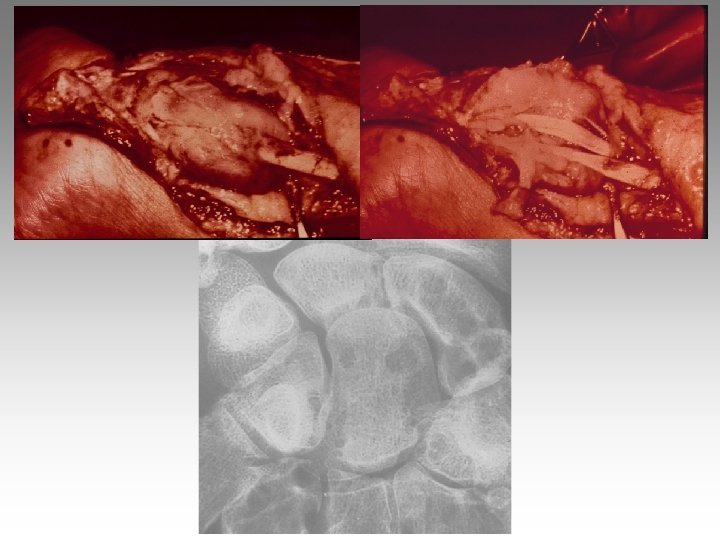

Hanche, T. , fract. fatigue Tendinites bursites, radic. Genou douloureux non traumatique Sémiologie Ponction +++ mécanique inflammatoire Rx inflammation Rx N Rx a. N < 40 ans interligne pincé Arthrose FT - FP contexte +++ > 40 ans Biologie, BS, Rx, IRM, écho interligne normal IRM AND, FF Paget, HOV ONA, OAN OAPH Ostéochond. infection IRM Arthroscopie Scinti. Os. LC Ménisque Coagul. PR, RP, Still, LED, SA…. Goutte, CCA AND ONA Ostéochondrite Pyogène, BK, Gono. , autres Hydarthrose X? Ostéochondromatose Synonite VN, T. , coag.

Genou douloureux non traumatique Sémiologie Ponction +++ mécanique inflammatoire Rx inflammation Rx N Rx a. N < 40 ans interligne pincé Arthrose FT - FP contexte +++ > 40 ans Biologie, BS, Rx, IRM, écho interligne normal IRM AND, FF Paget, HOV ONA, OAN OAPH Ostéochond. infection IRM Arthroscopie Scinti. Os. LC Ménisque Coagul. PR, RP, Still, LED, SA…. Goutte, CCA AND ONA Ostéochondrite Pyogène, BK, Gono. , autres Hydarthrose X? Ostéochondromatose Synonite VN, T. , coag.

Genou douloureux non traumatique Sémiologie Ponction +++ mécanique inflammatoire Rx inflammation Rx N Rx a. N < 40 ans interligne pincé Arthrose FT - FP contexte +++ > 40 ans interligne normal IRM AND, FF Paget, HOV ONA, OAN OAPH infection Biologie, BS, Rx, IRM, écho IRM Arthroscopie Scinti. Os. LC Ménisque Coagul. PR, RP, Still, LED, SA…. Goutte, CCA AND ONA Banal, BK, Gono. , autres Hydarthrose X? Ostéochondromatose Synonite VN, T. osseuse